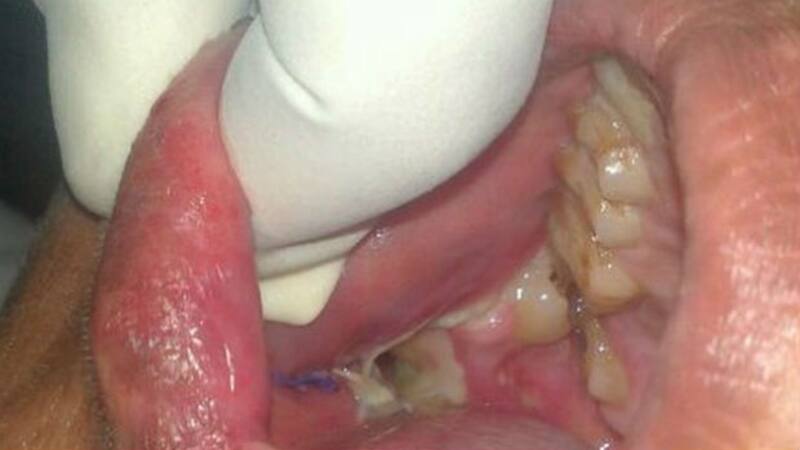

En la operación, se encontraron con un extraño panorama, iba desde pequeñas perlas a grandes y deformes piezas que se encontraban escondidas en la encía. Cuento corto: en la operación se impuso un récord mundial.

El doctor Dhiware (jefe del departamento dental) contó con sorpresa y orgullo que llegaron a contar la extracción de 232 dientes, un nuevo record mundial en la boca de cualquier ser humano.